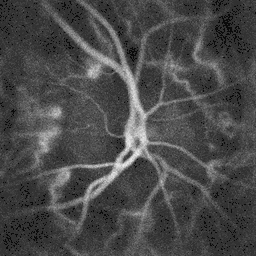

Blood flow in the retina and choroid in the optic disc region can be revealed non invasively by near-infrared laser Doppler imaging.[4] Laser Doppler imaging can enable mapping of the local arterial resistivity index, and the possibility to perform unambiguous identification of retinal arteries and veins on the basis of their systole-diastole variations, and reveal ocular hemodynamics in human eyes.[5] Furthermore, the Doppler spectrum asymmetry reveals the local direction of blood flow with respect to the optical axis. This directional information is overlaid on standard grayscale blood flow images to depict flow in the central artery and vein.[6]

Blood flow in the optic disc revealed by holographic laser Doppler imaging.[4] -

Local direction of blood flow with respect to the optical axis revealed by the Doppler spectrum asymmetry in out-of-plane retinal vessels by holographic laser Doppler imaging.[6] -